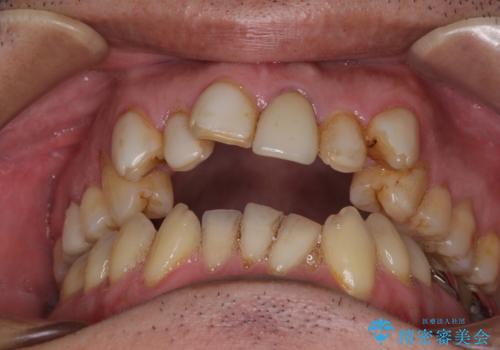

- 20年ほど前に被せた前歯のメタルボンドクラウンの色合いを気にして来院された患者様です。

2歯をオールセラミッククラウン(ジルコニアクラウン)にて補綴することとしました。

裏打ちが金属の場合、どうしても金属色を遮蔽しないとならないため、透明感のない色合いとなってしまいます。

土台の金属はグラスファイバーを含有したものに、クラウンの土台は強化セラミックとすることで、自然な前歯に仕上がりました。